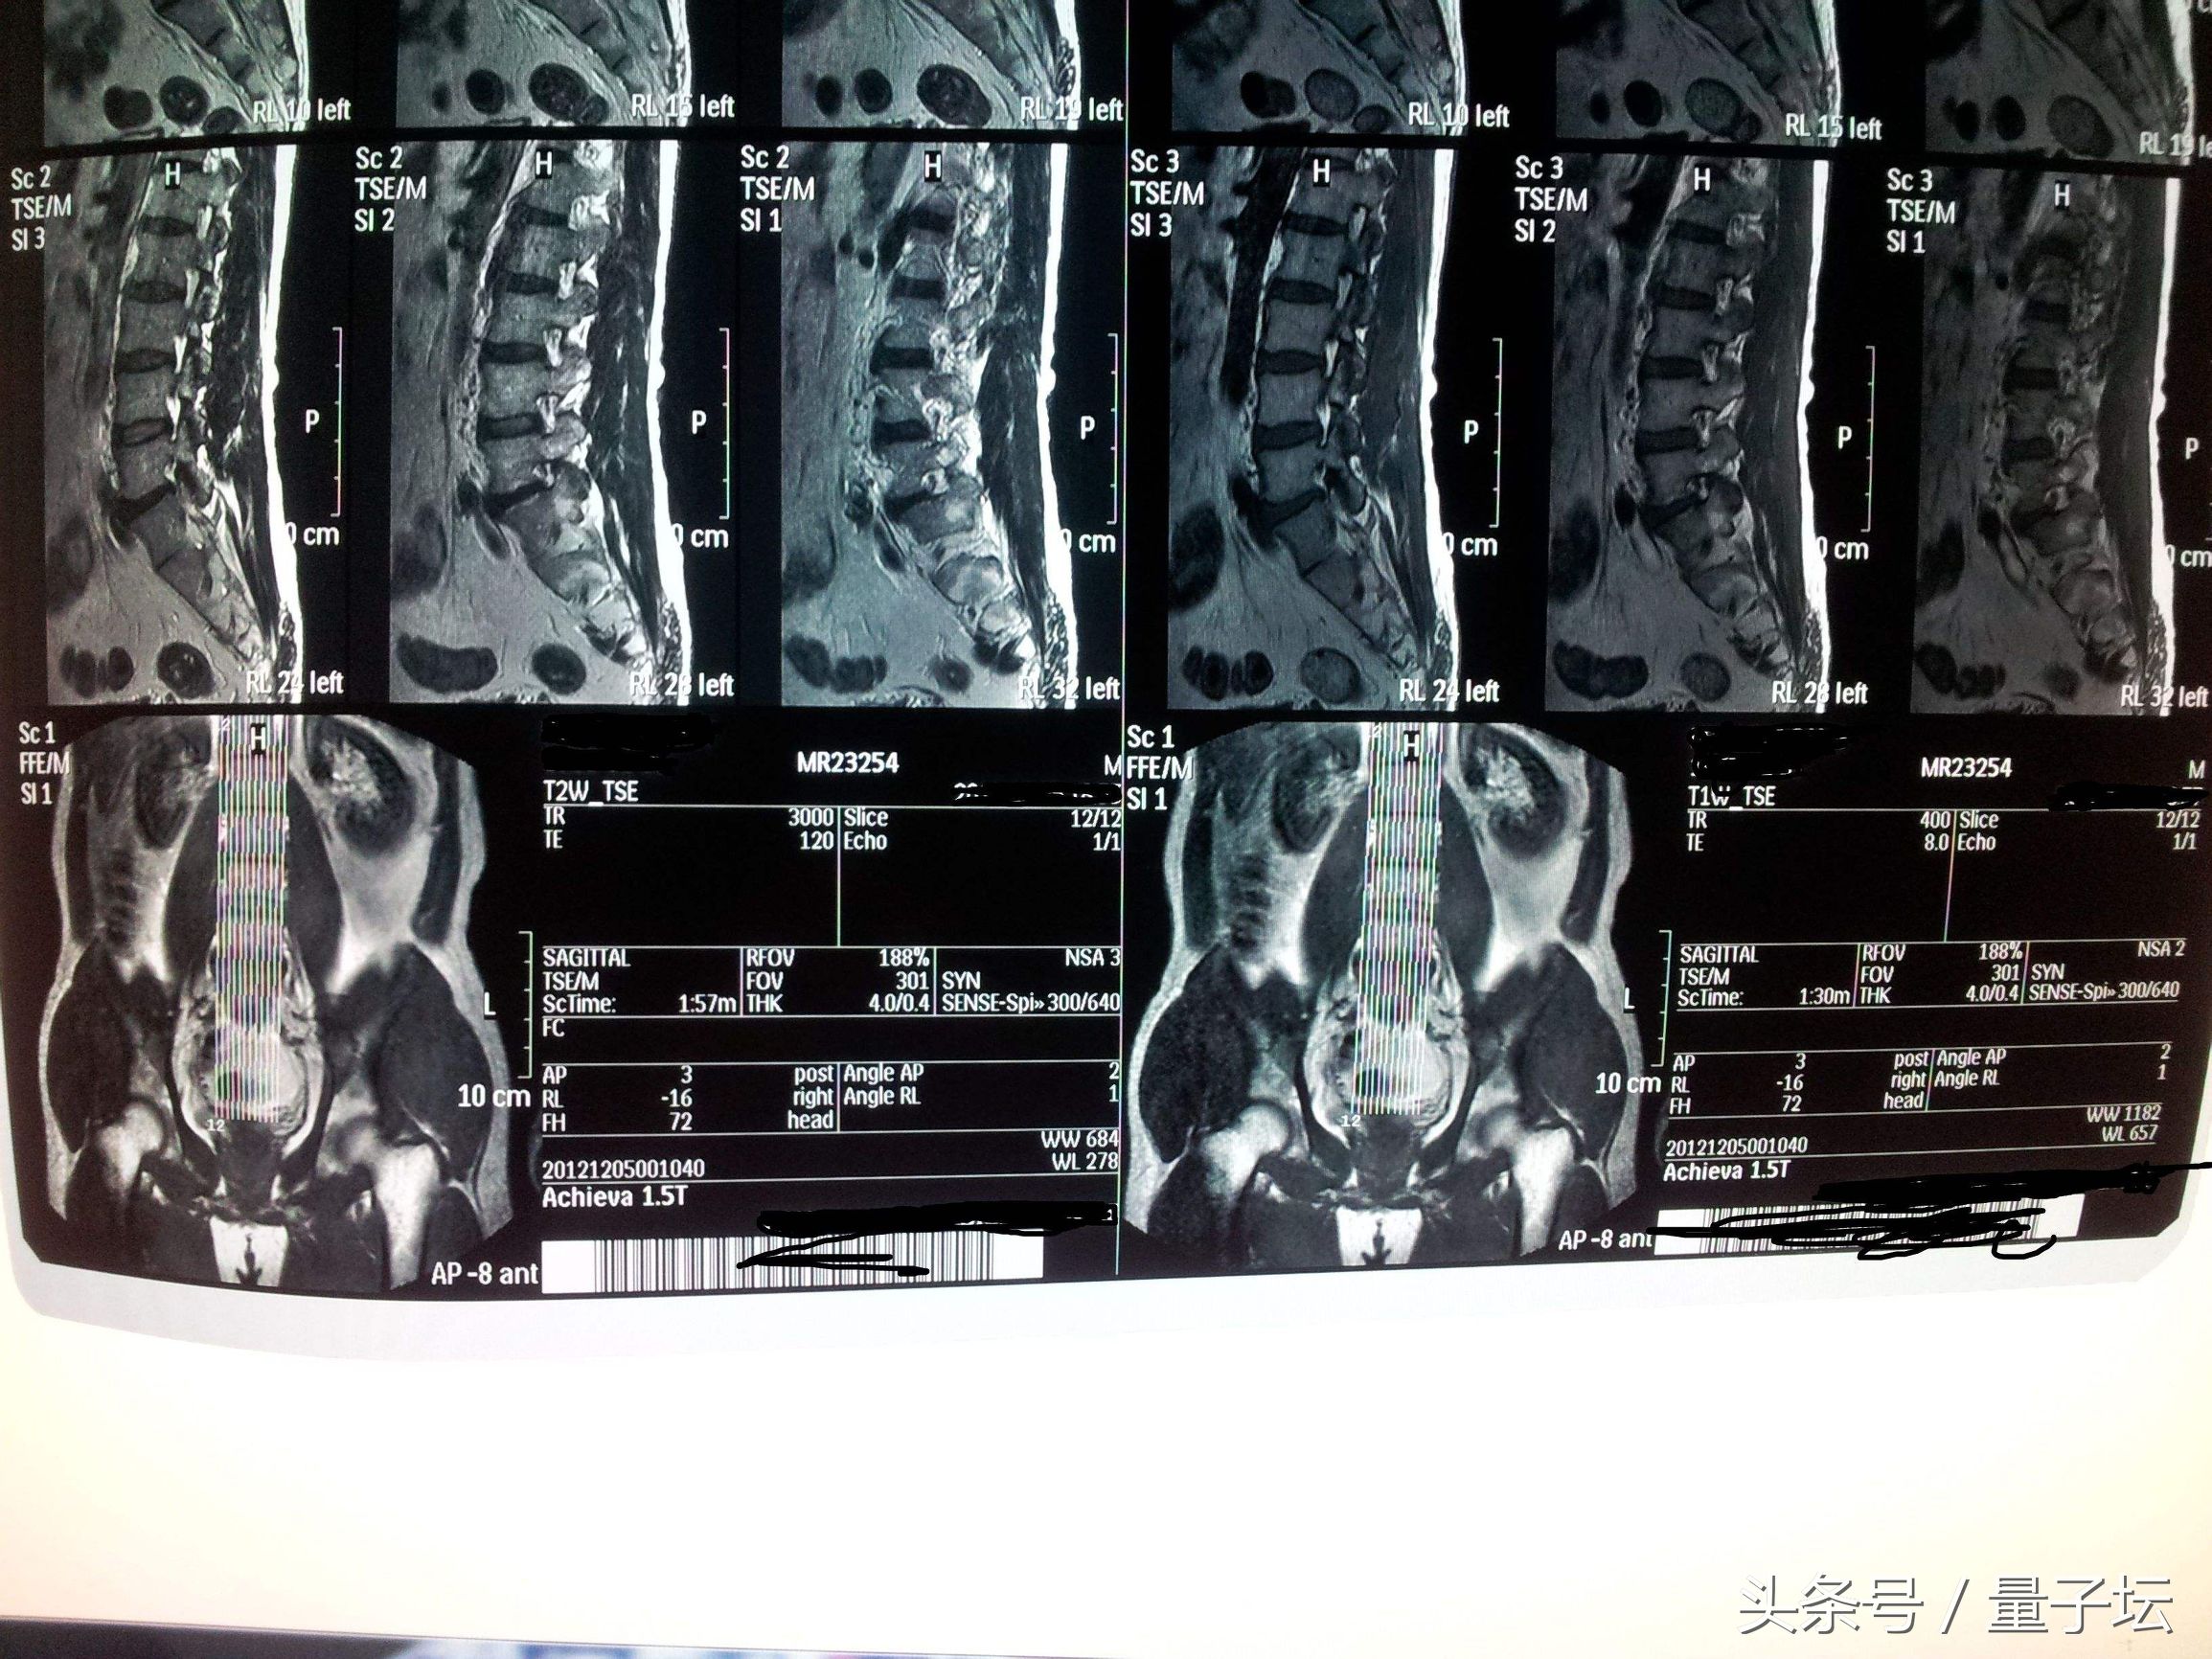

三、MRI:MRI是一种无创性检查技术,在脊柱脊髓疾病诊断方面有很大优越性。T1加权像上突出髓核的信号比CsF高,比硬膜外脂肪低,T2加权像突出髓核可表现为中或低信号,可显示腰椎间盘退变时信号减弱,椎问盘突出的隆起型、破裂型和游离型,以及进入椎管内髓核碎块移动后的位置,还可明确显示邻近椎间盘的变化及硬膜受压的部位和程度,尤其是全脊柱MRI检查可一次检查显示多节段病变。

MRI脊柱脊髓疾病诊断有很大优越性